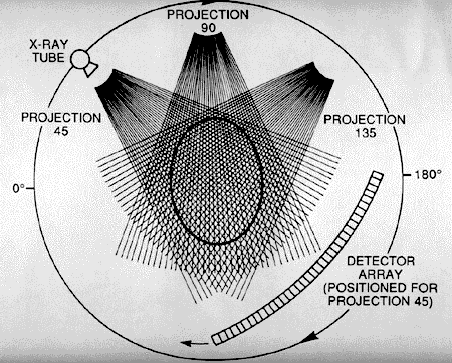

TERCERA GENERACIÓN 1976

• Rotación, Rotación

• 300-500 detectores

• Haz de RX cubre el ancho de la exploración

• Adquisición 2-10 Seg.

DETECTORES

TUBO DE RX